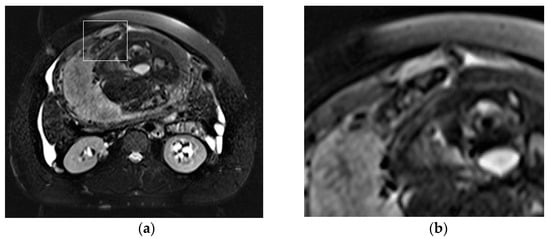

Placental/uterine bulge: deviation of the uterine serosa from the expected plane caused by abnormal bulge of placental tissue toward surrounding organs (typically toward the parametrium and bladder) can cause the uterus to take on an “hourglass” configuration due to widening of the lower uterine segment, resulting in a loss of the typical inverted pear-shape, best depicted on sagittal and/or coronal images. This finding showed a sensitivity and specificity for the diagnosis of PAS of 76.6% and 62.5% [72] (Figure 4). The specificity of this criterion increases where the bulging in the uterine contour is associated with a focal interruption of the myometrium [73].

MRI allows for the detection and characterization of large bladder flap hematomas (>4 cm in size) associated with UR or more often with UD (Figure 6).

When they are abscessed, large hematomas may cause fever and abdominal pain: in these patients, cross-sectional imaging reveals a peripheral-enhancing purulent collection between the lower uterine segment and the bladder wall (Figure 7).